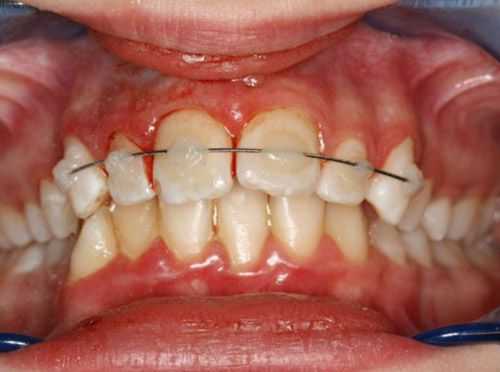

После проведённых лечебных мероприятий вывихнутый зуб иммобилизируют (обездвиживают). Для этого врач использует индивидуальную шину-каппу, изготовленную непосредственно на пациенте. В шину обязательно включают не менее двух здоровых зубов по обе стороны от неполного вывиха. Шину накладывают минимум на 5-6 недель.

Перед шинированием и в динамике лечения проверяют электровозбудимость (реакцию на электрический ток) сосудисто-нервного пучка. Понижение или отсутствие электровозбудимости не только в первые 1-2 недели после травмы не обязательно говорит о необратимых изменениях. Реакция пульпы может приходить в норму в течение нескольких месяцев. Но если обнаруживаются клинические признаки гибели пульпы, её необходимо удалить, а канал пролечить, иначе оставшаяся в канале мёртвая пульпа приводит к развитию острого периодонтита или периостита.